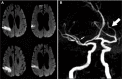

Stroke is the leading cause of disability in the USA and a major cause of mortality worldwide. One out of four strokes is recurrent. Secondary stroke prevention starts with deciphering the most likely stroke mechanism. In general, one of the main goals in stroke reduction is to control vascular risk factors such as hypertension, diabetes, dyslipidemia, and smoking cessation. Changes in lifestyle like a healthy diet and aerobic exercise are also recommended strategies. In the case of cardioembolism due to atrial fibrillation, mechanical valves, or cardiac thrombus, anticoagulation is the mainstay of therapy. The role of anticoagulation is less evident in the case of bioprosthetic valves, patent foramen ovale, and dilated cardiomyopathy with low ejection fraction. Strokes due to larger artery atherosclerosis account for approximately a third of all strokes. In the case of symptomatic extracranial carotid stenosis, surgical intervention as close as possible in time to the index event seems highly beneficial. In the case of intracranial large artery atherosclerosis, the best medical therapy consists of antiplatelets, high-dose statins, aggressive controls of vascular risk factors, and lifestyle modifications, with no role for intracranial arterial stenting or angioplasty. For patients with small artery occlusion (ie, lacunar stroke), the therapy is similar to that used in patients with intracranial large artery atherosclerosis. Despite the constant new evidence on how to best treat patients who have suffered a stroke, the risk of stroke recurrence remains unacceptably high, thus evidencing the need for novel therapies.